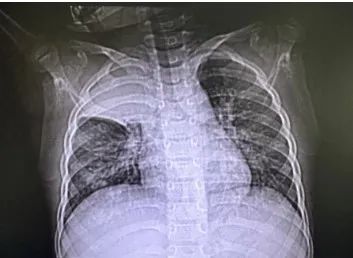

近日,4岁的小韩(化名)在父母的陪伴下,来到上海市儿童医院呼吸科就诊。“孩子三天前突发咳喘,后来还出现发热。”接诊的呼吸专科门诊医生通过胸片检查发现,小韩的两肺纹理增多,右上肺高密度影,可能存在感染性病变,随即将他收治到呼吸科病房。 手术现场 没想到的是,住院后小韩的血氧饱和度持续下降,最低仅89%,并出现了呼吸衰竭症状。“我们立即进行了肺部CT检查,发现孩子的右肺上叶影像完全消失,右肺中有少量胸腔积液。”呼吸科副主任顾浩翔第一时间与家长沟通,告知病情危重及后续治疗措施。“我们要马上进行电子支气管镜检查,先明确右肺上叶影像消失的原因,同时做病原学检测,才能对症下药。” 患儿右肺上叶“消失” 当电子支气管镜进入患儿肺部,顾浩翔发现右肺上叶开口处被白色痰栓完全填塞。“正常情况下右肺上叶三支开口的地方,被黏稠的痰栓完全堵塞,而且有继续增加蔓延的趋势。”顾浩翔进一步解释,这些痰液是患者肺部感染后,痰液没有及时排除,黏稠的炎性的分泌物不断积聚在气道内,最终堵塞气道造成的。 经呼吸科内镜团队讨论,最终使用较粗直径的(4.0mm)支气管镜,经内镜下2.0mm吸引孔,异物钳钳取联合负压吸引,仅用不到10分钟时间,取出两条长约5cm,看上去就像短树枝一样的完整塑型痰栓。 取出痰栓后的第二天,小韩病情明显缓解,缺氧症状消失,氧饱和度稳定于98%以上。在一周的抗感染治疗后,复查胸片予以出院门诊随访。 完整的塑型痰栓 经过病理分析,小韩得的是塑型性支气管炎,是儿科急危重症之一,往往较常见于重症支原体感染,会导致气道的内生性异物造成广泛性支气管堵塞,影响肺的通气功能,严重者发生呼吸衰竭甚至危及生命。“塑型性支气管炎起病急、进展快,可引起严重气道阻塞、呼吸困难,选择合适的支气管镜尽早取出塑形痰栓是治疗塑形支气管炎,避免呼吸衰竭,最行之有效的方法,但完整取出塑形痰栓难度较大。”顾浩翔提醒,一旦发现孩子突然出现发热不退,呼吸困难、面色发紫、烦躁不安等症状,应立即将孩子尽快送往医院救治,以免延误治疗危及生命。 上海市儿童医院呼吸科是我国最早开展可弯曲支气管镜检查的儿童专科医院之一,同时也是全国首批儿科呼吸内镜培训合作单位之一,是上海地区最大规模儿童呼吸专科。自2006年开展支气管镜检查至今,医院累计完成儿童局麻及全麻下支气管镜三、四级手术超10000例,年均完成千余例支气管镜检查及治疗,包括儿童重症肺炎、深部支气管异物、中央气道狭窄、中央气道占位、食管气管瘘、先天性气道畸形、肺部间质性疾病、肺动脉吊带、咯血等高难度病种。